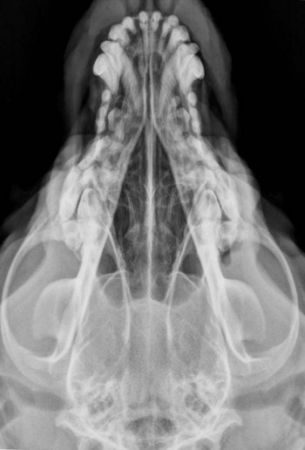

Craniu